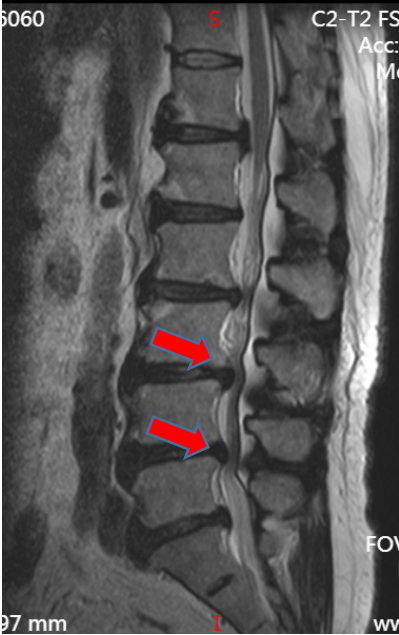

吴静晔主任(北京积水潭医院派驻专家、主任医师)仔细给张大爷做了查体,又结合影像学检查,很快有了结论:“您这不是普通老腰病,是腰椎 3-4、4-5 节段椎管变窄了,就像水管被压扁,里面的神经受了压迫,才会又疼又麻、走不远。”

术前核磁影像

之前连坐 10 分钟都疼,现在能坐起来吃早饭,术后一周更是能在病房里慢慢走几圈,复查的磁共振显示:之前狭窄的椎管已经恢复正常宽度,神经压迫彻底解除。